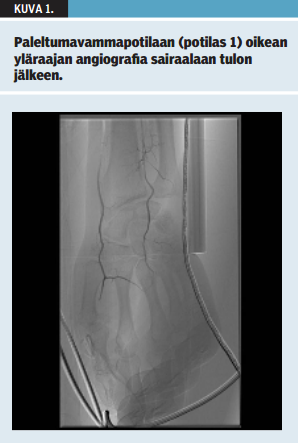

Potilas 1 on 49-vuotias päihdeongelmainen mies. Aikaisempina sairauksina hänellä on ollut mahalaukun ja ruokatorven tulehdus. Potilas löydettiin päihtyneenä lumihangesta makaamasta. Ensiavussa tärykalvosta mitattu ruumiinlämpö oli 31 °C. Ulkoisia vammoja potilaalla ei todettu. Potilasta lämmitettiin kehonulkoisin lämpöpeittein, ja kestokatetrin kautta mitattu lämpötila nousi nopeasti yli 35 °C:een. Kliinisessä tutkimuksessa kädet olivat kalpeat ja verenkierrottoman oloiset lämmityksen jälkeen. Kummastakaan kädestä ei saatu dopplerlaitteella mitattua valtimoverenkiertosignaalia rannetasolta tai sormista. Potilaalle tehtiin paleltumavammapotilaan protokollan (taulukko 1 «»1) mukaisesti yläraajojen verisuonten varjoainetutkimus (angiografia). Molempien yläraajojen värttinä- ja kyynärvaltimot täyttyivät erittäin hitaasti, eivätkä sormivaltimot eivät täyttyneet luotettavasti (kuva 1 «»2). Potilaalle annettiin protokollan (taulukko 2 «»3) mukainen valtimon sisäinen liuotushoito, jota jatkettiin kahden vuorokauden ajan. Lisäksi potilaalle aloitettiin asetyylisalisyylihappo- ja ibuprofeiinilääkitys. Vuorokauden kuluttua tehdyssä kontrollivarjoainekuvauksessa verenkierto oli parantunut (kuva 2 «»4). Liuotushoidon päättymisen jälkeen käsien verenkierto oli kliinisesti hyvä ja Allenin testillä arvioiden molempien rannevaltimoiden verenkierto oli normalisoitunut. Potilas kotiutui 5 vrk:n sairaalahoidon jälkeen. 6 viikon kuluttua paleltumavammasta potilaan käsissä oli vielä tunnon alentumaa ja kylmäherkkyyttä. Amputaatioita tai leikkaushoitoa ei tarvittu.